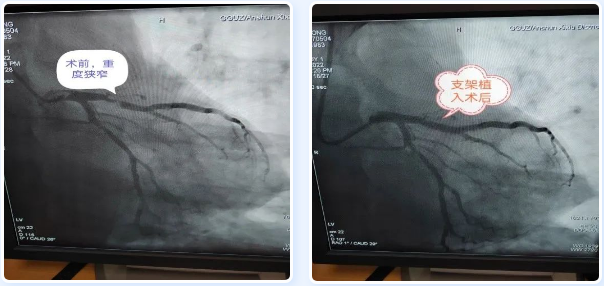

12时58分,患者被送入导管室,冠脉造影结果提示左冠状动脉近端次全闭塞,来自广医五院帮扶专家、安顺市西秀区人民医院胸痛中心主任张铭华博士带领2位医生通力合作,迅速开通了堵塞的血管,并植入药物支架,李先生顺利转危为安。14时00分,手术顺利完成,术后李先生胸痛症状消失,生命体征平稳,顺利转危为安。